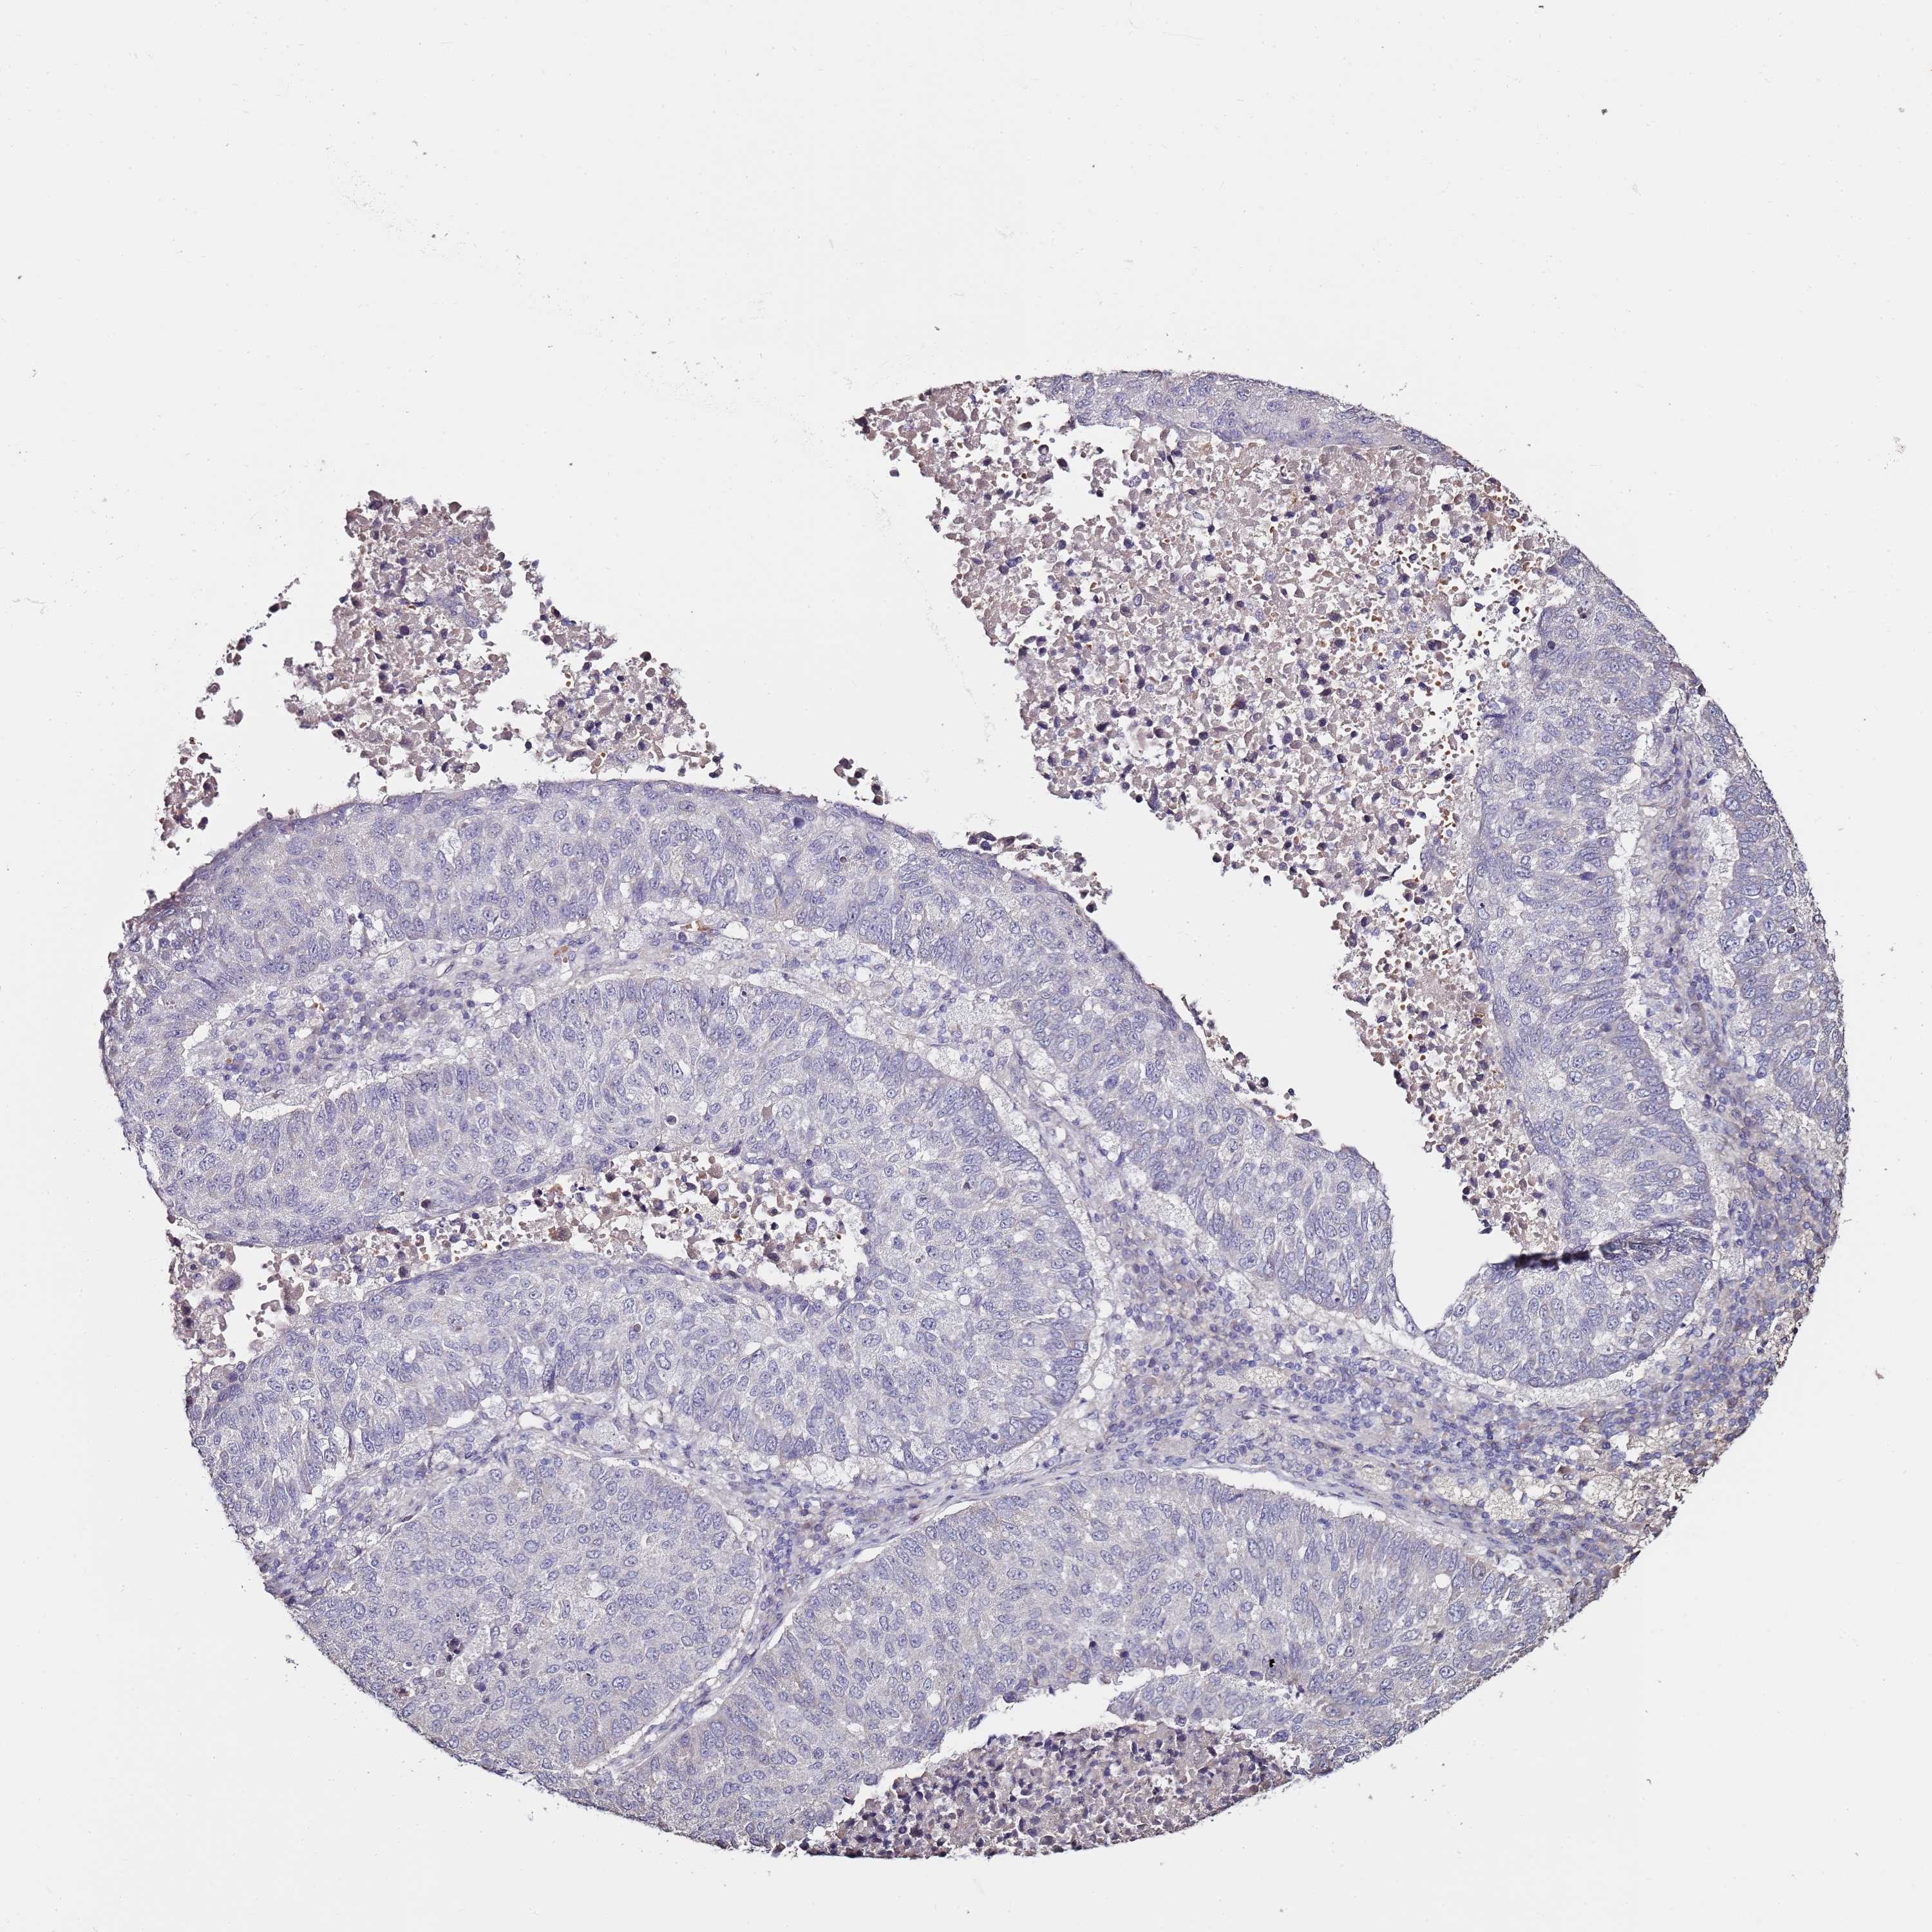

CANCER LUNG CANCER Show tissue menu

C3orf80 is not prognostic in Lung Adenocarcinoma (TCGA)

C3orf80 is not prognostic in Lung Adenocarcinoma (validation)

C3orf80 is not prognostic in Lung Squamous Cell Carcinoma (TCGA)